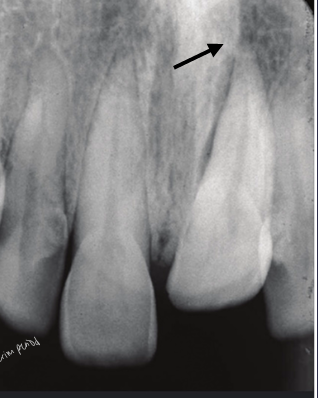

cervical root fracture

-outcome/treatment will depend on age of patient

-adult: don’t worry, can extract and implant

-child/adolescent: don’t want to extract- could compromise the alveolus; want to preserve the root, extract coronal segment, bury root under bone and use retention (essix retainer) for esthetics, when pt turns 18 could do implant then since the ridge will have been preserved